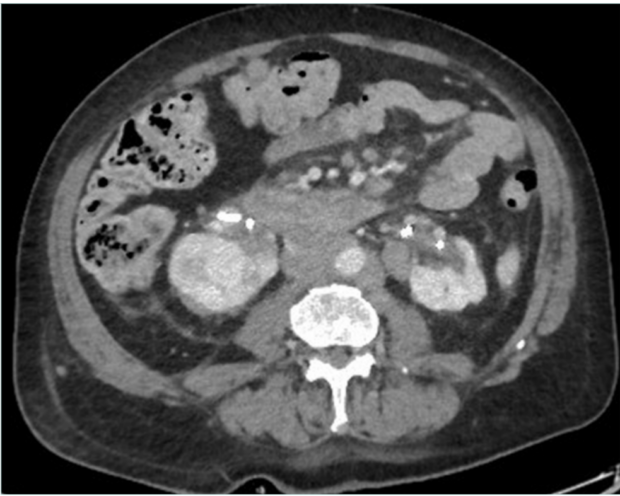

Computed tomography (CT) venography is an easily available and the most commonly used imaging technique as it can be performed through peripheral venous access with injection of 150 mL of iodinated contrast agent with acquisition at 90 and 120 seconds4 (Figures 2 and 3). According to a recent Delphi consensus, it should be the first-line imaging technique.5

Figure 2. Computed tomography (CT) scan in a patient with metastatic liver and ascites with inferior vena cava occlusion.

Both techniques can depict the tumoral and vascular lesion(s). CT angiography and CT venography (or MRV) are mandatory in order to look for tumor vascularization, IVC status (obstruction or occlusion [Figures 2 and 3]) and collateral pathways. According to O’Sullivan, CT venography should be proposed in all cancer patients with lower-limb edema.2